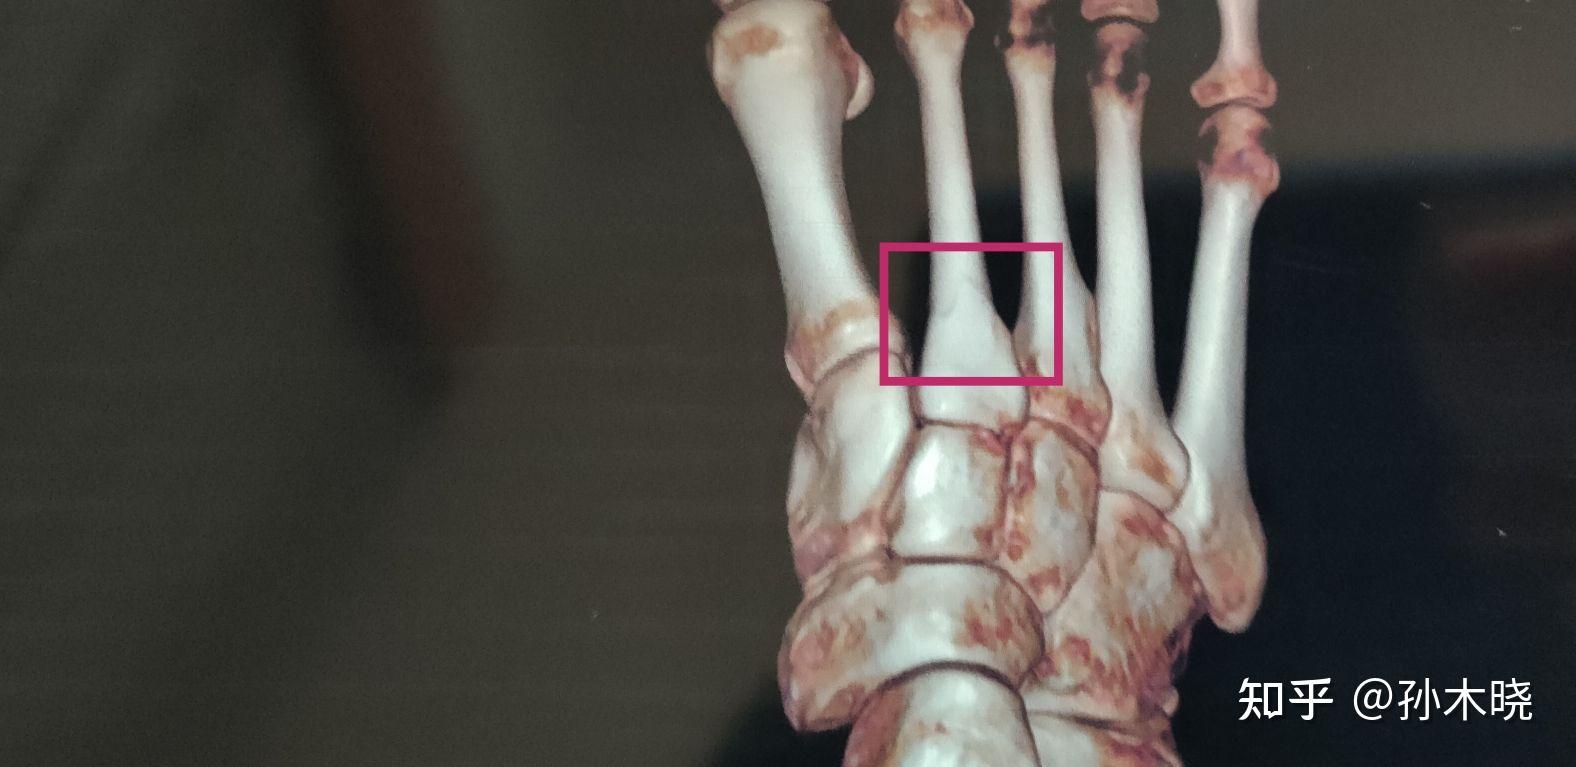

第二跖骨

在此图中,第二跖骨骨折导致第三跖骨至第五跖骨横向移位.

红框标注处,左足第2跖骨陈旧性骨折,骨折线已基本愈合,断端对位对线好